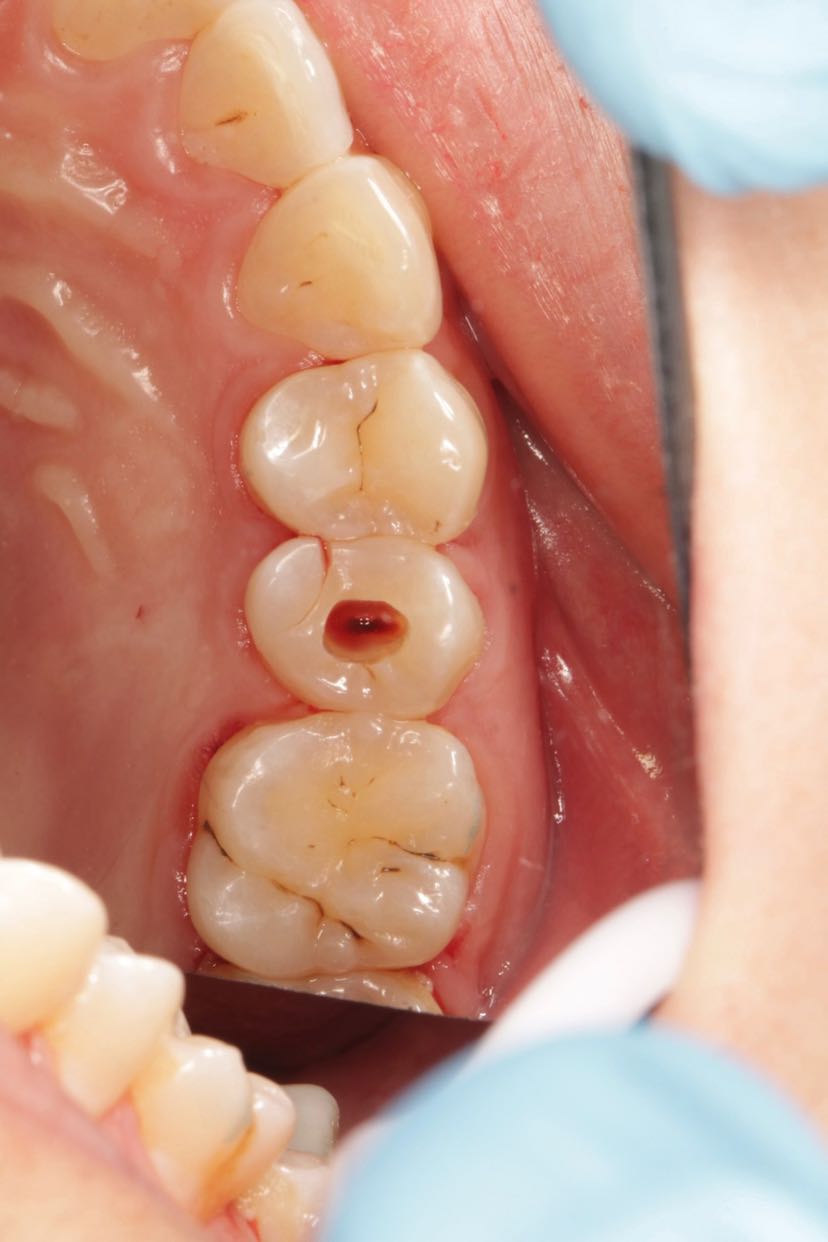

不可修复性牙折的诊断与治疗一例_检查_裂纹_远中